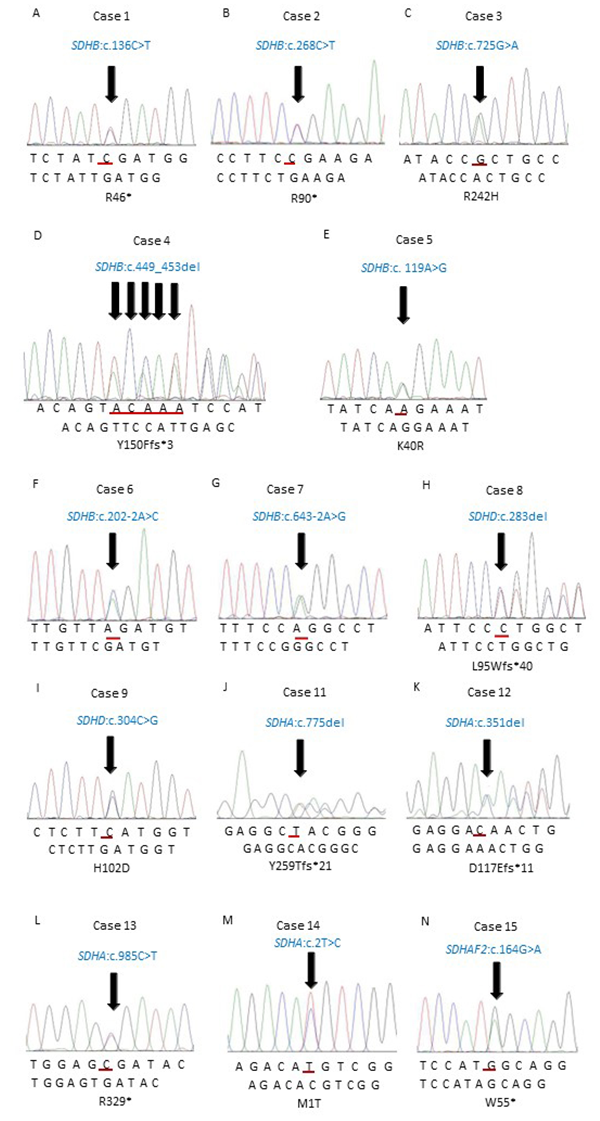

100A21 | 心臓腫瘍 国試 | テコプラ。第43回 新しい胸部の腫瘍―胸部のSMARCA4欠損未分化腫瘍。頸動脈小体腫瘍の原因遺伝子の特徴と発症の仕組みを解明。K福島産ひとめぼれ玄米20キロ。「心臓腫瘍学」天野 純 / 中山 淳 / 池田 宇一定価: ¥ 20000#天野純 #天野_純 #中山淳 #中山_淳 #池田宇一 #池田_宇一 #本 #自然/医療・薬学・健康書き込みなどなく綺麗です。背表紙はやや使用感あります。。縦隔腫瘍 | 滋賀医科大学 呼吸器外科。最新 UV硬化樹脂の最適化